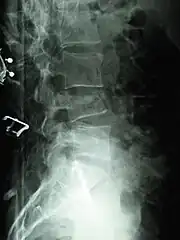

A compression fracture is a collapse of a vertebra. It may be due to trauma or due to a weakening of the vertebra (compare with burst fracture). This weakening is seen in patients with osteoporosis or osteogenesis imperfecta, lytic lesions from metastatic or primary tumors,[1] or infection.[2] In healthy patients, it is most often seen in individuals suffering extreme vertical shocks, such as ejecting from an ejection seat. Seen in lateral views in plain x-ray films, compression fractures of the spine characteristically appear as wedge deformities, with greater loss of height anteriorly than posteriorly and intact pedicles in the anteroposterior view.[3]

Compression fractures are usually diagnosed on spinal radiographs, where a wedge-shaped vertebra may be visible or there may be loss of height of the vertebra. In addition, bone density measurement may be performed to evaluate for osteoporosis. When a tumor is suspected as the underlying cause, or the fracture was caused by severe trauma, CT or MRI scans may be performed.